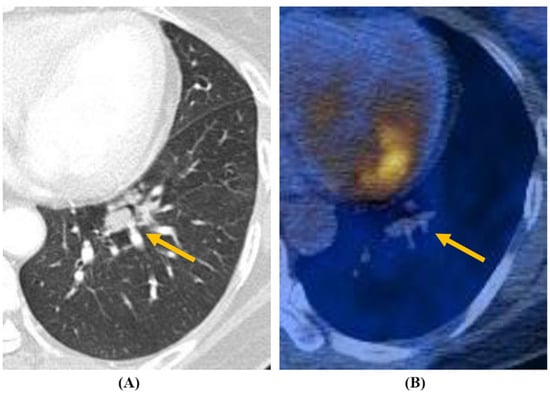

| PET uptake (SUVmax ≥ 2.5) (n = 20) | 18/20 (90) | 8 (40) | 10 (50) | 0.224 |